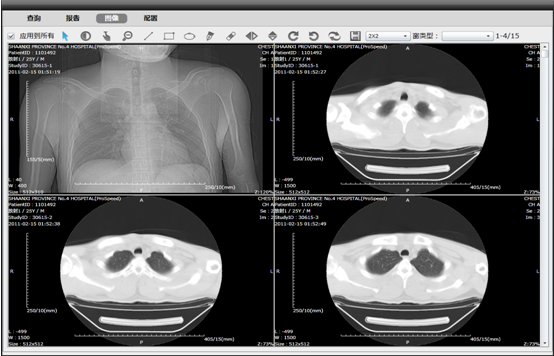

全院级医学影像管理平台(PACS)

亚创PACS率先实现将医院所有检查设备集成至PACS系统之中,包括放射检查设备、超声检查设备、内窥镜、核医学检查设备、心电图等,为医院PACS系统的未来扩展打下坚实基础。针对不同类型的检查设备,采用不同的集成技术。以标准DICOM接口为主,同时采用非标准数字接口技术、通用网络虚拟输出技术等,实现将不同类型的检查设备真正统一集成至PACS并发布到临床科室实现共享,且对于硬件设备没有特定的要求。